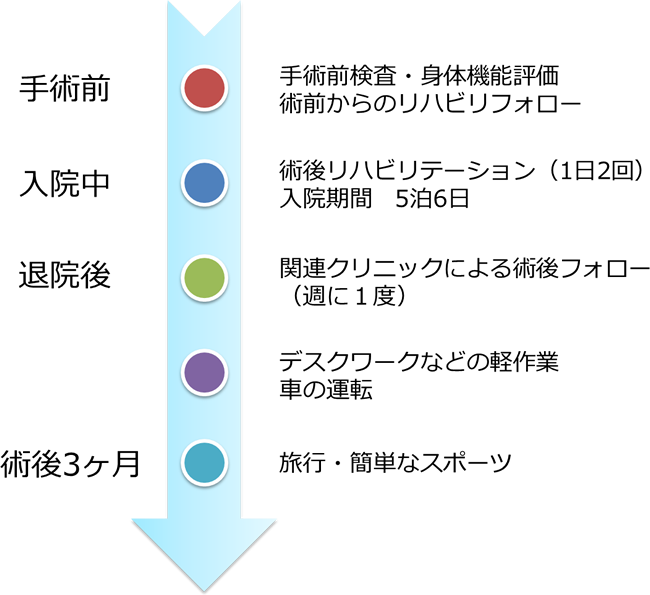

手術前から社会復帰までの流れは?

手術を申し込まれてから約1-2か月間の手術前リハビリを実施しています。

また手術までの間にソーシャルワーカーによる手術前説明を行います。

入院は手術当日です。

術後のリハビリは1日2回行い、5泊6日での退院となります。

退院後は執刀医による定期的な診察や外来リハビリ(週1-2回)を行います。